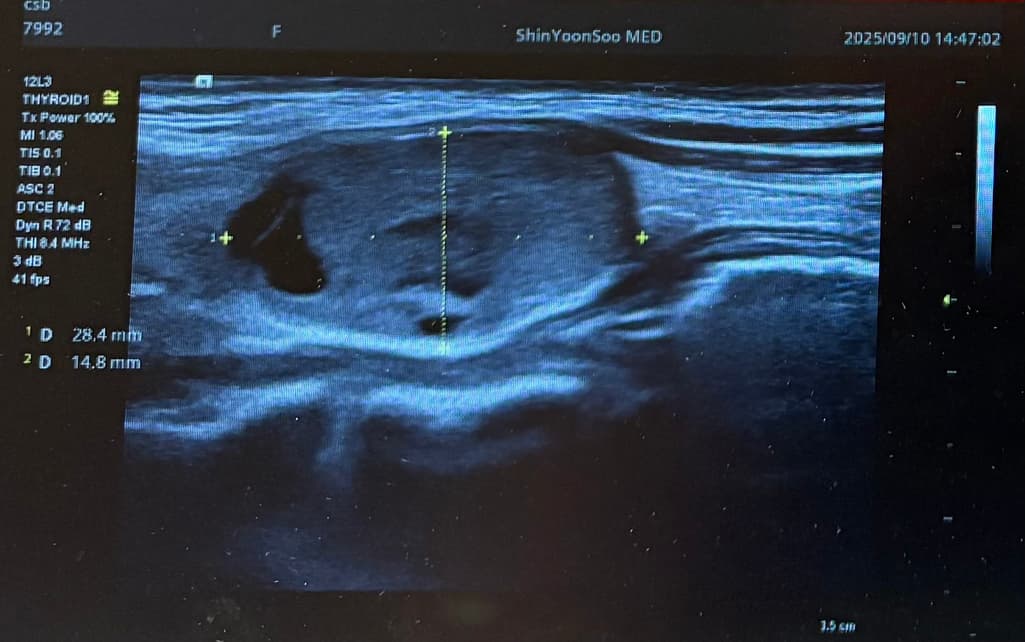

Lt 1ower lobe

1.88x1.4x2.84cm mixed nodule Lt middle lobe 1.22x0.37x 0. 49cm의 nodule 소견으로(의뢰서에 적혀있던 내용) 초진 보러가니 초음파 사진만 보시고는 식도와 신경에 들러붙어있고 점점점 커지면서 추후엔 응급수술로 진행될 수 있으니 아직 젊을때 빠르게 수술로 떼어내자고 결론은 수술밖에 없다고 냅다 수술일정 한달뒤로 잡고왔습니다.

왼쪽에 약 3cm가량으로 전체가 혹일거라며 상황이 많이 안좋은거고 위치가 안좋다고 하셔서 다음주에 수술전 검사 받은 후 2주뒤 입원으로 일정이 잡혔는데 보통 세침검사 또는 총생검사 후 수술 여부가 결정되는걸로 알고있는데 ..

저는 세침이나 총생검사 받지도 않고 바로 수술이 잡혔고 절개 형식으로 반절제, 수술 후 조직검사 진행 예정으로 상병명도 모르고 아무것도 모르는 상태인데 이런 경우가 흔한가요….?

위치가 그렇게 안좋은건가요..? 주변에서 어떻게 보면 동맥부근이랑도 붙어있다는것 같이 말하네요..